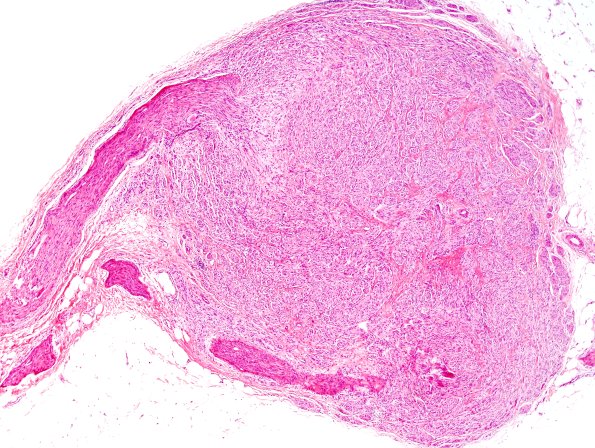

Washington University Experience | PERIPHERAL NEUROPATHY | 19 TRAUMATIC INJURIES | 1A2 Neuroma, traumatic (Case 1) H&E 1A

At the end of this peripheral nerve is a haphazard proliferation of Schwann cells and nerve fibers with admixed collagen, forming a terminal nodular structure on the proximal nerve stump. (H&E)